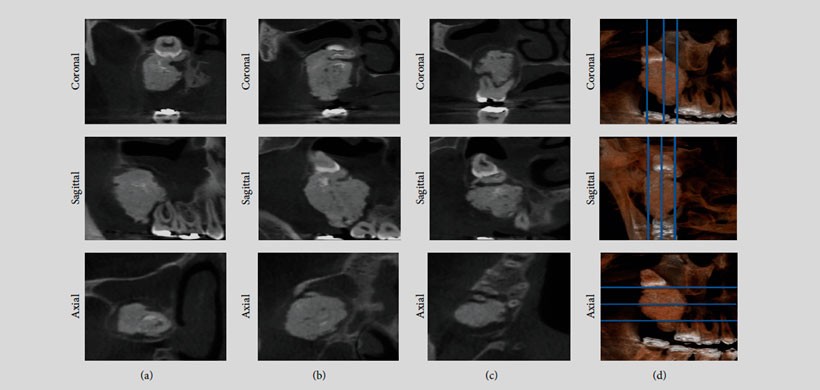

El presente reporte es un paciente de sexo masculino que  fue remitido al Departamento de Cirugía Oral y Maxilofacial, Universidad de Montes Claros, con la principal queja de dolor en la región posterior de la maxilar derecho. Las reformaciones panorámicas y los cortes obtenidos de la CBCT mostraron una masa radiopaca irregular rodeada por una distinta llanta radiolúcida asociada con el tercer molar superior derecho, en estrecha relación con el seno maxilar.  (Figura 1 y Figura 2) Posterior a la cirugía, se realizó un escaneo de micro – CT de la muestra obtenida y se obtuvo la adquisición usando una máquina SkyScan 1172 (Bruker SkyScan , Aartselaar , Bélgica ). En la cual se observó material en la periferia de la lesión ( Figuras 3 ( b) y 3 ( c) , flechas blancas ), que es compatible con esmalte de los dientes y áreas hipodensas (Figuras 3 (b) y 3 (C), flechas negras)  compatibles con el tejido de la pulpa siendo el diagnóstico definitivo  de odontoma complejo .

Figura 2: Cortes axiales, sagitales y coronales de la tomografía volumétrica de haz cónico

Figura 3 : (a) Histopatología del odontoma. (b – c) imágenes micro – TC del odontoma complejo. (b) Sin zoom. (C) Con el zoom .